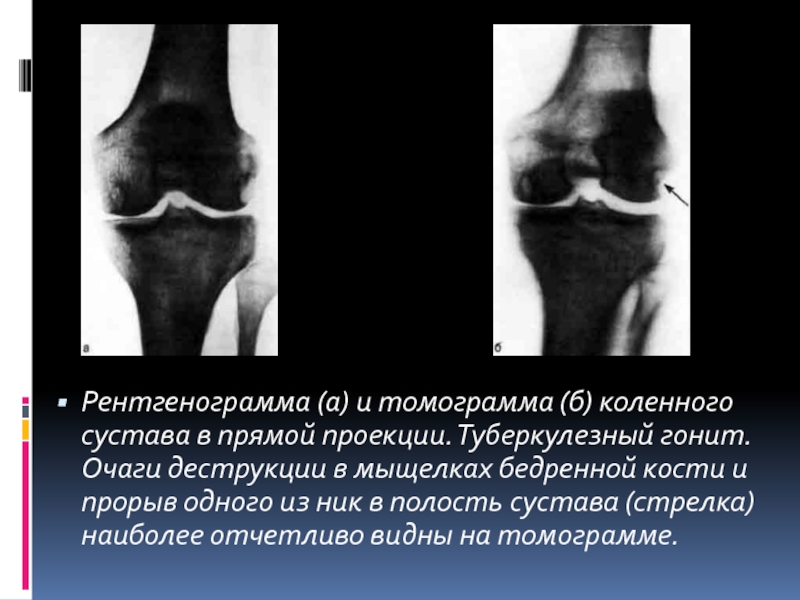

Периферический костно-суставной туберкулез

Периферический костно-суставной туберкулез — это термин, используемый для экстраспинального скелетного туберкулеза, который поражает суставы или кости. Обычно поражаются длинные опорные кости, относительно часто встречается артрит коленного или тазобедренного сустава, нередко встречаются заболевания бедренной кости (включая туберкулезный бурсит вертела) (таблица). Иногда поражаются ребра, крестцово-подвздошные и грудинно-ключичные суставы. Туберкулез — одна из наиболее частых причин остеомиелита ребер.Экстраспинальный туберкулезный остеомиелит проявляется в виде холодного абсцесса с отеком и только легкой эритемой и болью, и его можно ошибочно принять за опухоль.

Суставной туберкулез — это медленно прогрессирующее хроническое заболевание, которое в 90% случаев проявляется как моноартрит, обычно бедра или колена [25] (таблица).Предыдущее травматическое повреждение может быть провоцирующим событием. Самым ранним проявлением является боль, которая может предшествовать появлению признаков воспаления в течение недель или месяцев. Лихорадка и системные симптомы обычно отсутствуют.